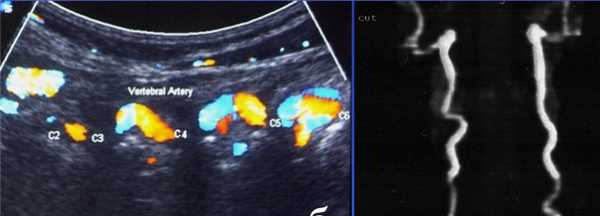

Главными исследованиями при подозрении на являются МРТ шейного отдела позвоночника, реже КТ шейного отдела позвоночника, МРА позвоночных артерий (ПА) и дуплексное сканирование позвоночных артерий. Часто к этому списку добавляют МРТ головного мозга и МРА сосудов Виллизиева круга. Самыми частыми находками при МРА позвоночных артерий и дуплексном сканировании (ДС) является их извитость без системного дефицита кровотока.

Извитость позвоночных артерий при ДС в режиме ЦДК и МРА.